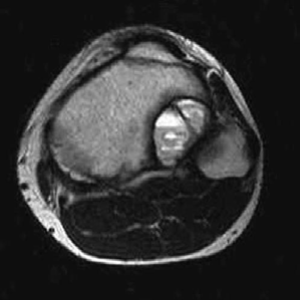

Orthopaedic oncology Structured oral examination question 2: Enchondroma Figure 7.2 Enchondroma. EXAMINER : T…